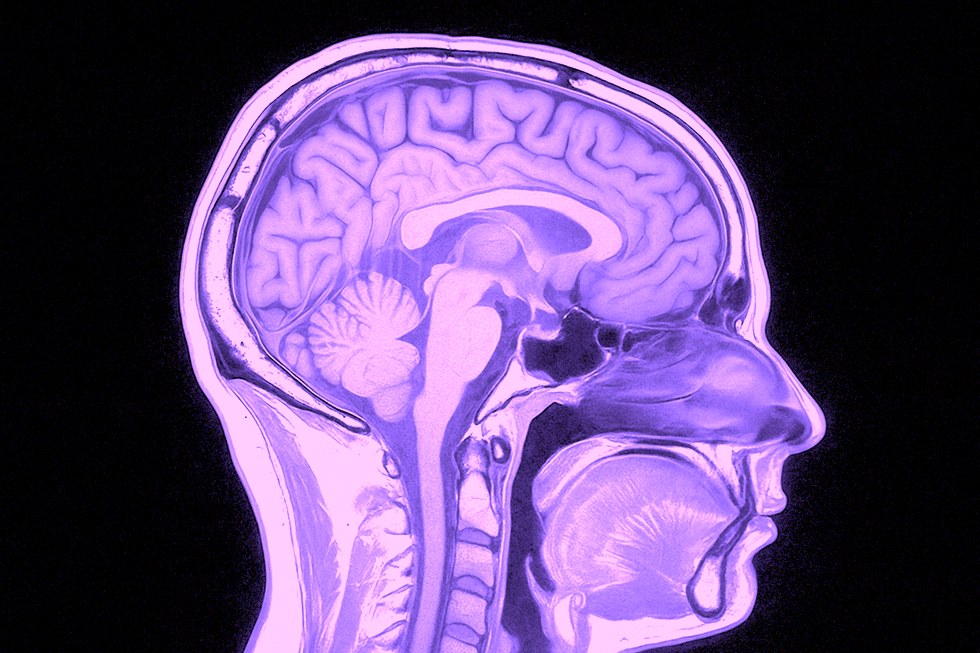

En MR-undersökning av hjärnan är ett smärtfritt, strålningsfritt och mycket detaljerat sätt att se hur hjärnan mår. Den används både för att utreda symtom som huvudvärk eller minnesproblem, och för att utesluta allvarliga tillstånd som tumörer eller blödningar.

En MR-undersökning (magnetresonanstomografi) är en modern och helt strålningsfri metod som ger otroligt detaljerade bilder av hjärnan. Tekniken använder ett starkt magnetfält och radiovågor för att skapa bilder av hjärnans mjukvävnader – vilket gör det möjligt att se saker som inte syns på vanliga röntgenbilder eller datortomografi. Det bästa? Det är helt smärtfritt och innebär ingen exponering för röntgenstrålning.